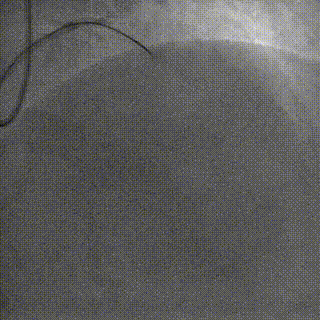

手术影像

左冠优势,LM、LCX未见狭窄,TIMI3级;LAD近段CTO,TIMI0级

RCA细小,近中段狭窄40%-50%,TIMI3级;远端可见LAD侧枝血流